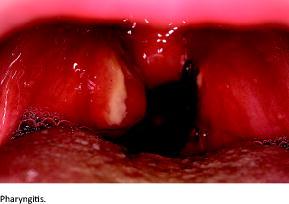

Concomitantly with periodic fever, patients have at least one of the following characteristic symptoms: pharyngitis, aphthous stomatitis and/or cervical adenitis. As not all characteristic symptoms need to be present to make the PFAPA diagnosis, there will be variation in the patients’ clinical presentation. This becomes apparent when our findings are examined for the distribution of patients according to characteristic symptoms and are compared with the findings of other studies. Erythematous pharyngitis was present in 80.6% of the patients in our study, and exudative pharyngitis in 61.3%. Other studies have reported pharyngitis in 65-96% of patients [5, 7, 10, 12]. We found that 48.4% of our study population had aphthous stomatitis. In other studies, this was the case in 38-67% of patients [5, 7, 10, 12]. Lastly, 96.8% had cervical adenitis in our study, but this was only the case for 61-77% of patients in other studies [7, 10, 12].